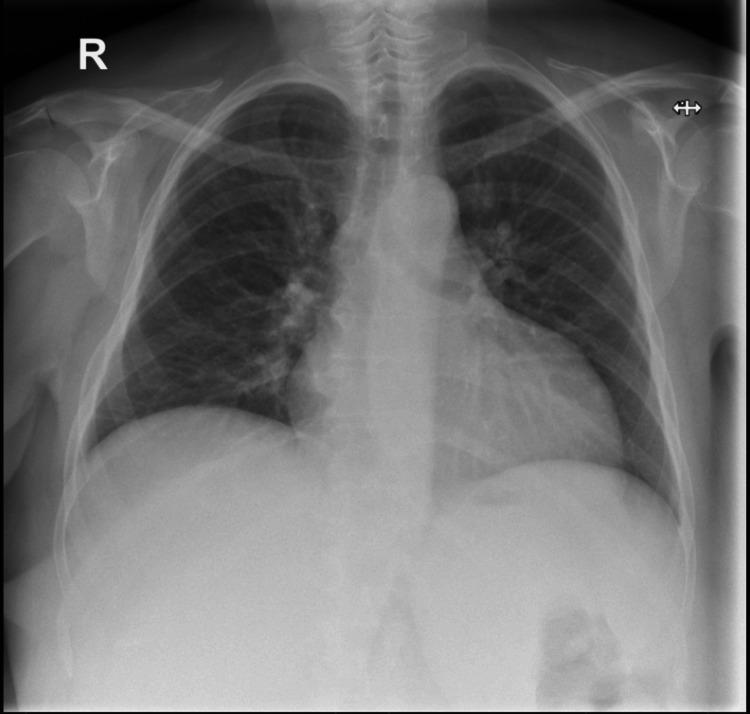

Iliopsoas abscess is a rare infection that presents with a triad of fever, back pain, and hip pain. However, due to the anatomical proximity of the psoas muscle to various structures, an abscess in this region can manifest with nonspecific symptoms, leading to potential misdiagnosis and delayed diagnosis, which can be fatal. We report a case of a 54-year-old female who presented to the emergency department with right-sided flank pain and symptoms resembling lower motor neuron disorder. Initial investigations were inconclusive until an MRI revealed a large retroperitoneal collection in the right perinephric space and iliopsoas muscle, likely of urological origin, with no spinal abnormalities. Intravenous gentamicin was initiated. A subsequent contrast-enhanced CT scan of the abdomen and pelvis confirmed a right posterior perinephric collection. Ultrasound-guided drainage was performed, and a pigtail catheter was placed in situ for continuous drainage along with targeted antibiotics based on culture and sensitivity.

髂腰肌脓肿是一种罕见的感染性疾病,表现为发热、背痛和髋部疼痛三联征。然而,由于腰大肌与各种结构在解剖位置上相邻,该区域的脓肿可能表现为非特异性症状,导致潜在的误诊和诊断延迟,这可能是致命的。我们报告一例54岁女性,因右侧胁腹疼痛及类似下运动神经元疾病的症状就诊于急诊科。最初的检查结果不明确,直到磁共振成像(MRI)显示右肾周间隙和髂腰肌有一个大的腹膜后积液,可能源于泌尿系统,且无脊柱异常。开始静脉注射庆大霉素。随后的腹部和盆腔增强CT扫描证实右肾后有积液。进行了超声引导下引流,并置入一根猪尾导管进行持续引流,同时根据培养和药敏结果使用针对性抗生素。